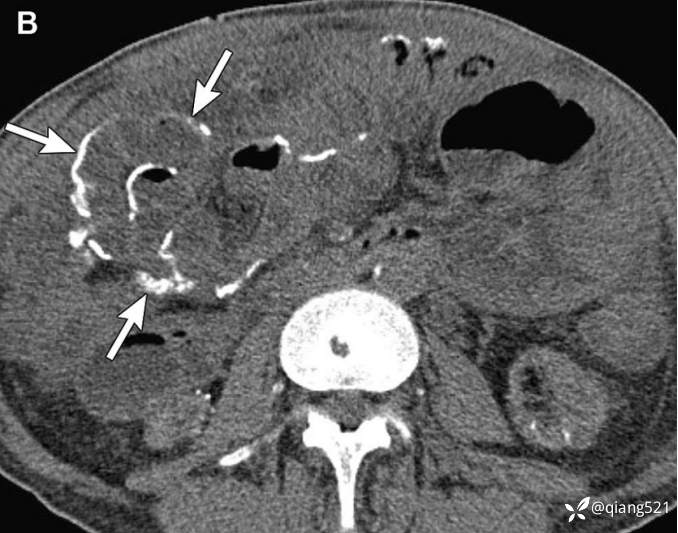

1例21岁男性腹膜圆形细胞瘤。

经下腹部(A)和骨盆(B)的轴位CECT显示腹部和骨盆(箭头)的多灶性不均匀密度软组织肿块。C18-FDG-PET显示腹膜植入物(箭头)和右侧膈下间隙(箭头)摄取FDG。